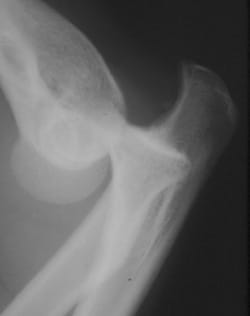

Les luxations du coude : qu’est-ce que c’est ?

C’est une perte de congruence de l’articulation du coude = humérus + radius + ulna. La stabilité du coude repose sur le système ligamentaire le Ligament collatéral médial (LCM), le Ligament collatéral latéral (LCL).

La luxation du coude survient lors de chute sur la main, bras en extension (le plus fréquent). Stress en valgus, rotation forcée lors de choc direct (sport, accident moto). Luxations le plus souvent postéro-latérales.

Impotence fonctionnelle avec perte de l’alignement épitrochlée-olécrane-épicondyle.